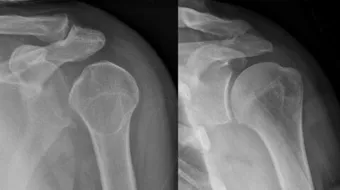

أعراض الإصابة بخلع الكتفيحدث خلع الكتف نتيجة خروج مفصل اليد العُلوي عن تجويف الكتف؛ نتيجة السقوط عليه، أو تعرُّضه للإصابة، ويُرافق خلع الكتف ظهور العديد من

يحدث خلع الكتف نتيجة خروج مفصل اليد العُلوي عن تجويف الكتف؛ نتيجة السقوط عليه، أو تعرُّضه للإصابة، ويُرافق خلع الكتف ظهور العديد من الأعراض، وفيما يأتي بعض منها:[1]

- تشوُّه الكتف؛ أي ظهور بروز في الجزء الأماميّ، أو الخلفيّ من الكتف.